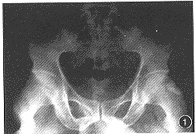

例1男,38岁。右股内侧疼痛、麻木3个月,加重20d,伴同侧髋关节酸沉,行走、咳嗽、用力排便时症状加重。曾在外院以“股内侧筋膜炎”治疗2个月无效,于1990年12月15日收入我院。查体:股内收肌轻度萎缩,股内侧自腹股沟至膝上3cm处皮肤触痛觉减退,股内收肌肌力3级,右髋关节伸、屈正常,外展时疼痛沿股内侧放射至膝。右下肢肌电图提示闭孔神经中度损伤,骨盆X线片显示,右侧闭孔内上方有一骨化影向闭孔内延伸(图1)。诊断为右闭孔神经卡压综合征。于腰麻下,自右耻骨支向股内侧下方做弧行切口,切断长收肌肌腱止点,找出闭孔神经,向上分离至闭孔处。术中见闭孔膜部分骨化,挤压闭孔神经及闭孔血管,被挤压的局部神经明显变细,外膜增厚,无弹性。切断部分闭孔内肌并切除部分骨化物及闭孔膜,充分松解闭孔神经,止血后缝合长收肌腱性部分。术后10d拆线,下床活动,髋关节及下肢症状消失。3个月后肌力恢复至5级,局部皮肤感觉恢复。

图1 骨盆X线片示,右侧闭孔内上方有一骨化影响闭孔内延伸